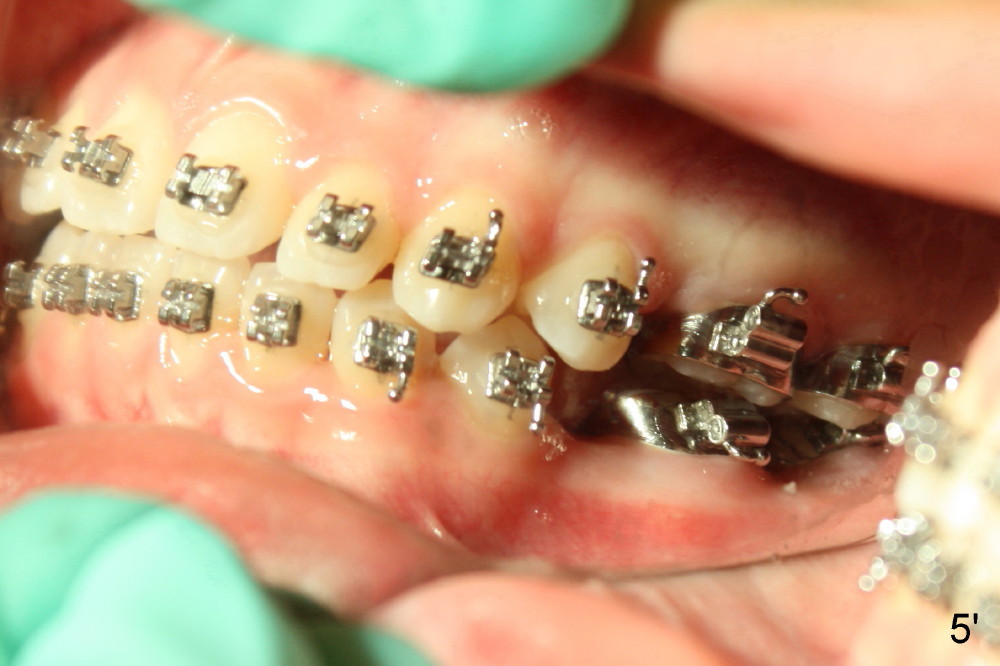

A 13-year-old Asian girl seeks orthodontic treatment for crowding. The lower 2nd bicuspids are congenitally missing (Fig.1,8), whereas the upper right one rotates 180° and the upper left is partially impacted (Fig. 1, 7). The lip muscles strain when the lips close (Fig.3). Orthodontic treatment started with extraction of four affected teeth (#4,13, K and T) 6 months ago. .018' niti wires are being used. Dental midlines do not coincide preop and intraop (Fig.4,4'). Pre-op front view shows that the upper dental midline coincides with the facial one (Fig.1'). There is Class I canine and molar relationship on the right (Fig.5,5',9,9'); open bite on the left (Fig.6,6',10,10').

Update: The left open bite was closed less than one month by wearing elastics between upper and lower teeth (Fig. 6'''). The occlusal plane and midline improve (Fig.4''). Wires have gradually changed to .016x.016, .016x.022 and now .018x.025 with power chains. All the spaces are closed except the one in LR (Fig.7''-10''). What I cannot accomplish is to fix meisal (Fig.5'' (white line), 9'') and lingual (Fig.8'' arrows) inclination of LR molars, although elastic is instructed to be placed between UR7 buccal and LR7 lingual. The rectangular wires could be twisted to fix lingual inclination. Which should be done first: LR space or LR molar inclination? Click each figure for magnification.